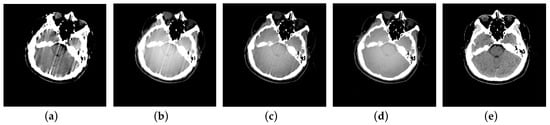

3.3. Patient Scan Experiments